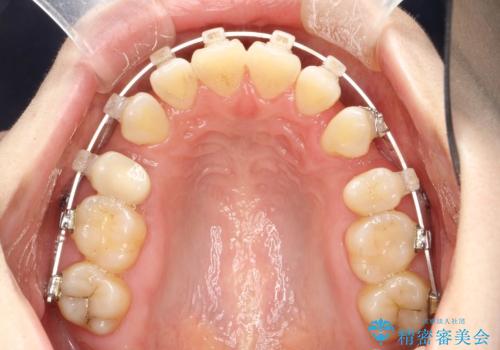

抜歯をして前歯を下げ、ガタつきを取り除く ワイヤー矯正

- 上顎両側第1小臼歯、下顎左側第2小臼歯の3本を抜歯、ラビアルのワイヤー矯正を計画した。